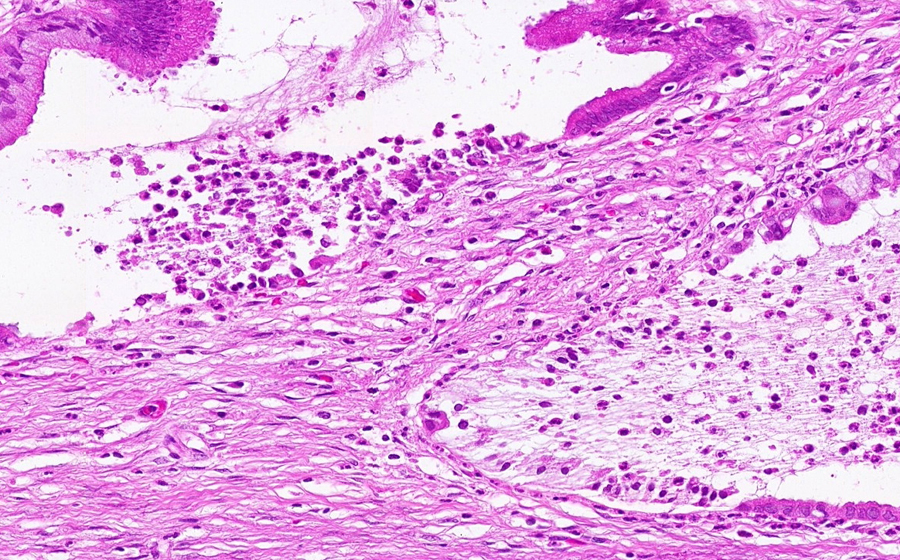

Image 6 - 400X

Slide 3 - Image 6